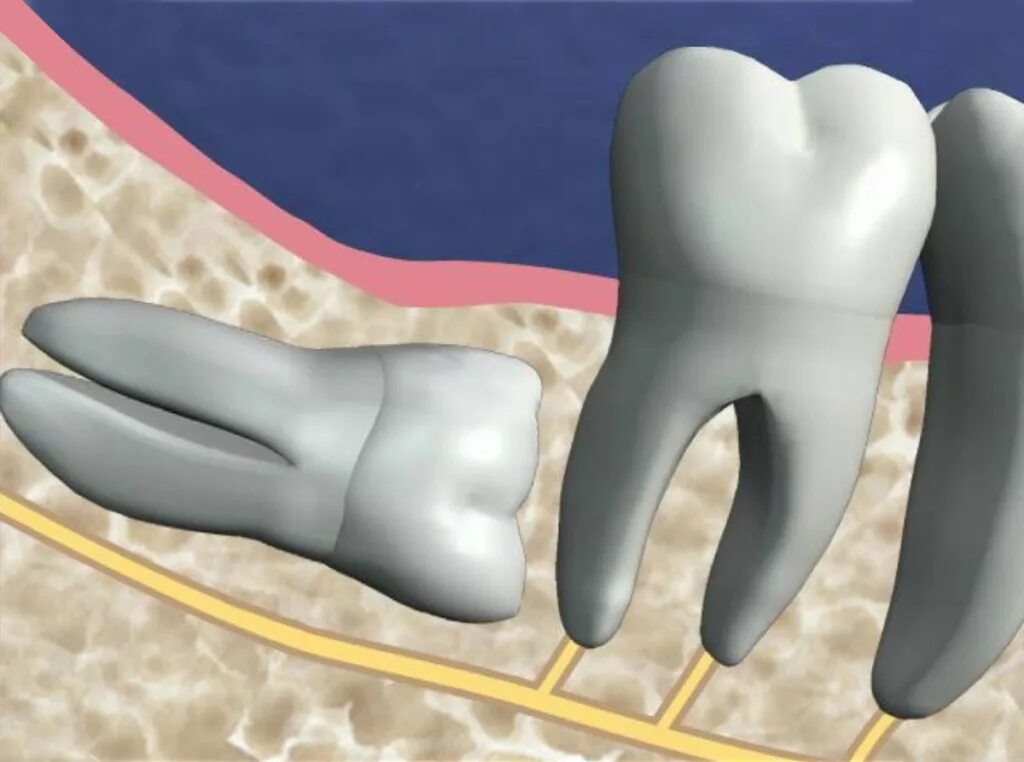

Зуб дистопирован